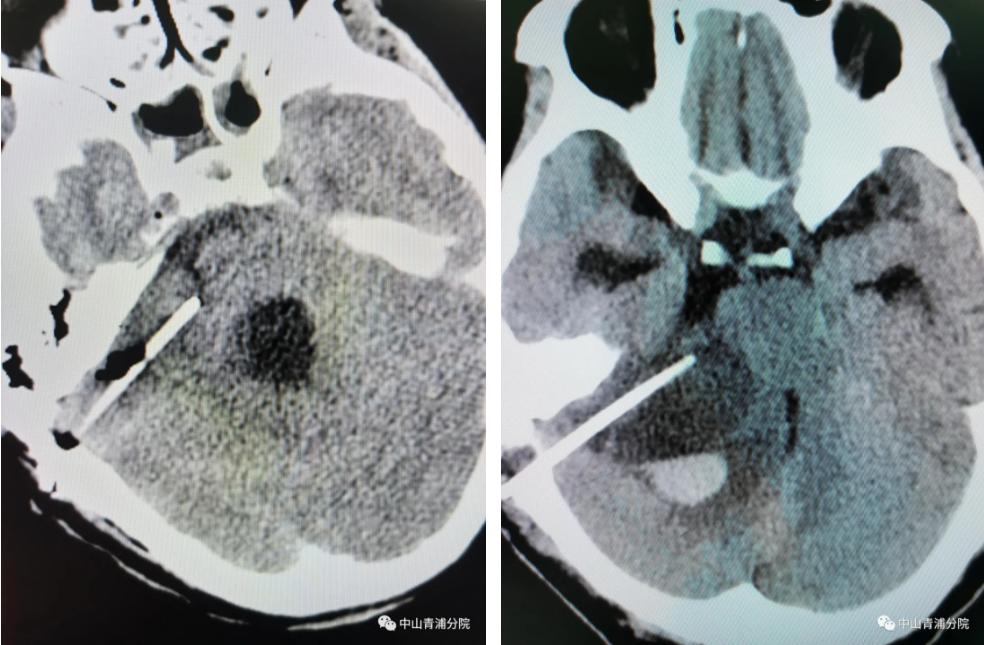

正当神经外科团队为张阿姨研究最佳手术方案时,张阿姨再次出现意识不清,呼吸急促且心率增快。全力救治下,张阿姨的生命体征平稳下来,李季林副主任医师团队为患者施行ommaya囊植入+囊肿穿刺引流术,术中顺利,术后再次转入外科重症监护室治疗。几天后,张阿姨醒了……

(术后头颅CT影像)